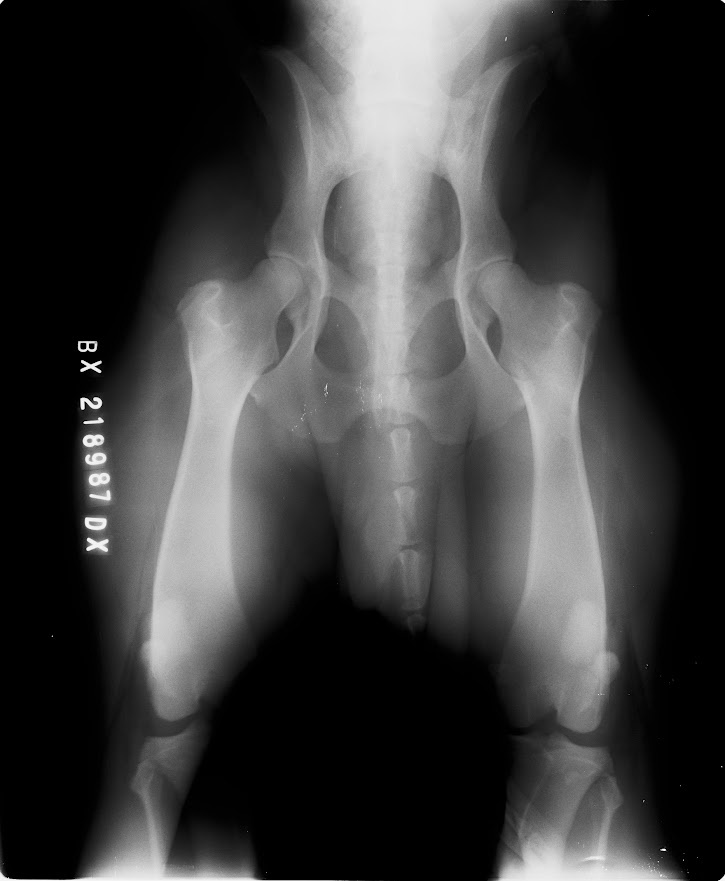

Hledáme nevěstu pro mladého psa BD s PP, Butch Coolidge dei Mastini del Goya, import Itálie, DKK AA, DLK 00, srdce OK, vyšetření sperma, vynikající pohyb, V1, CAC, Národní vítěz ČR, stáří 3 roky, perfektní povaha